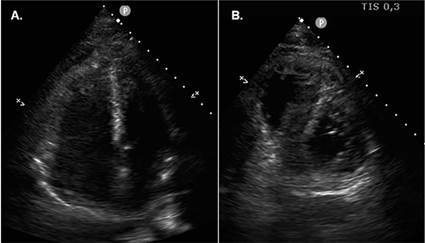

evidence of collections/abscesses. A brief transthoracic echocardiography was

performed in the ER, which rose the suspicion of

thrombus/endocarditis. The subsequent transesophageal

echocardiogram documented a thrombus adherent to the pacemaker leads. There was

After treatment with LMWH for a week, there was a

complete resolution of the thrombus (shown in Fig. 2). The patient was also seen in the immunohemotherapy clinic, and thrombophilia was discarded.

Fig. 2. Transesophageal echocardiography bicaval plane.

Post anticoagulation image of the pacemaker leads, without evidence of thrombus